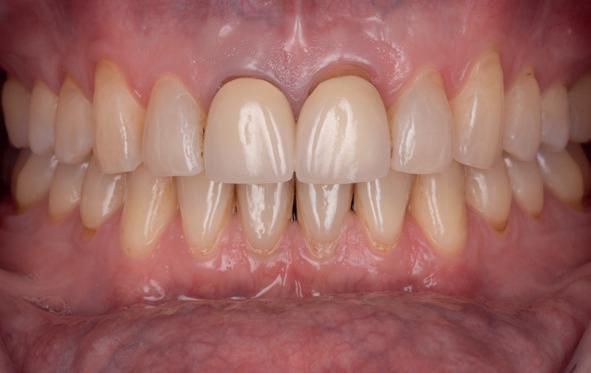

18. Etsbrug frontbeeld

19. Etsbrug palatinaal